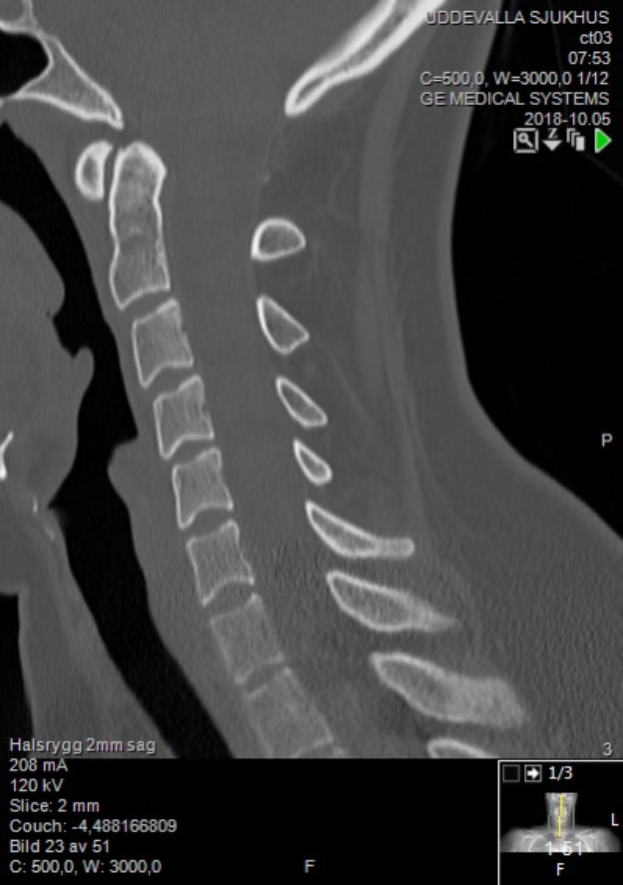

Ein Röntgenbild eines Mannes mit einem sichtbaren Bruch in der Mitte, das auf einem Computerbildschirm mit Text und Zahlen angezeigt wird.Irmtrud Bolzmann